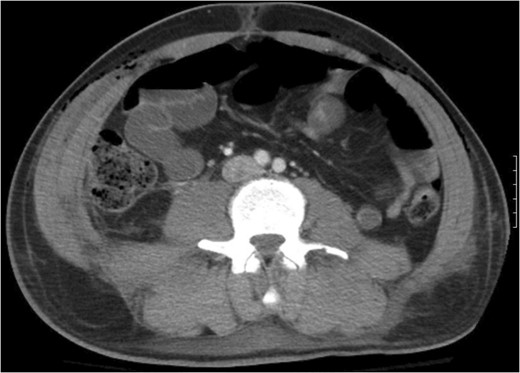

A 43-year-old male patient presented with a right-sided traumatic lumbar hernia after a blunt mechanism. The patient had been pinned between a dirt-mover’s claw arm resulting in a crush mechanism. He sustained injuries to the lumbar spine, sacrum, abdominal wall and 12th rib. On presentation, he did not have clinical or radiographic evidence necessitating abdominal exploration and was observed in a monitored setting. Computed tomography imaging demonstrated a Grynfeltt defect with herniation of the ascending colon and cecum through an area defined by the 12th rib, quadratus lumborum and internal oblique (Figures 1 and 2). After several days of observation and recuperation, the patient continued to have significant pain overlying the hernia site. We electively brought him to the operating room on post-injury Day 4. A laparoscopic repair of the traumatic hernia was performed. Key operative steps included: (i) Wide exposure of the hernia defect via incision of the peritoneum and transversalis as well as mobilization of the ascending colon and duodenal sweep (Figures 3 and 4). (ii) Primary repair of the defect with intra-corporeal suturing of the oblique musculature (Figures 5 and 6). (iii) Placement of an underlay mesh with appropriate redundancy at least 4 cm in all directions around the defect and seating against the iliac crest (Figure 7). Post-operative imaging demonstrates obliteration of the hernia defect and restoration of the abdominal wall (Figures 8 and 9). The patient has recovered, returned to the work force and has no pain or bulge at the repair site 6 months after injury.

With the patient in the left lateral decubitus the herniated right colon spontaneously reduces and the hernia is demonstrated.

Step 1 begins with incision of the peritoneum overlying the hernia.